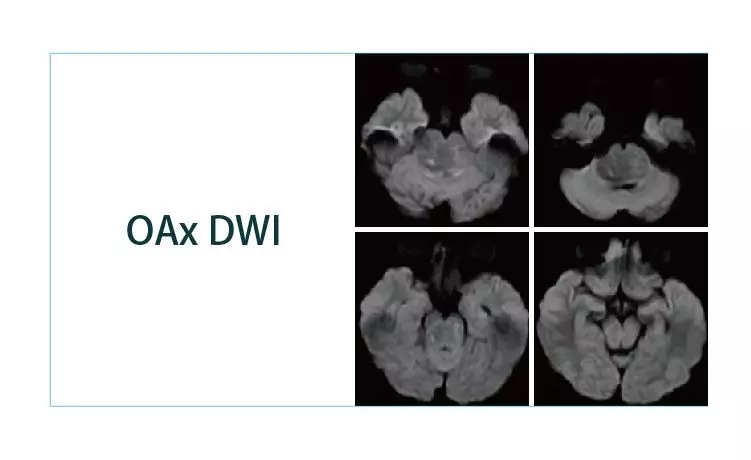

【朗润影像档案】20190329磁共振影像病例结果讨论